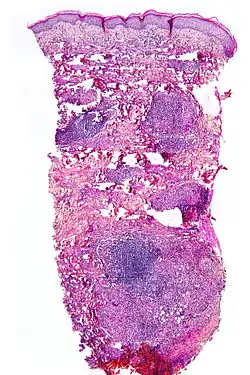

Micrograph showing necrobiosis lipoidica in a punch biopsy

NL is diagnosed by a skin biopsy, demonstrating superficial and deep perivascular and interstitial mixed inflammatory cell infiltrate (including lymphocytes, plasma cells, mononucleated and multinucleated histocytes, and eosinophils) in the dermis and subcutis, as well as necrotising vasculitis with adjacent necrobiosis and necrosis of adnexal structures.[23] Areas of necrobiosis are often more extensive and less well defined than in granuloma annulare. The presence of lipid in necrobiotic areas may be demonstrated by Sudan stains. Cholesterol clefts, fibrin, and mucin may also be present in areas of necrobiosis. Depending on the severity of the necrobiosis, certain cell types may be more predominant. When a lesion is in its early stages, neutrophils may be present, whereas in later stages of development, lymphocytes and histiocytes may be predominant.[24]